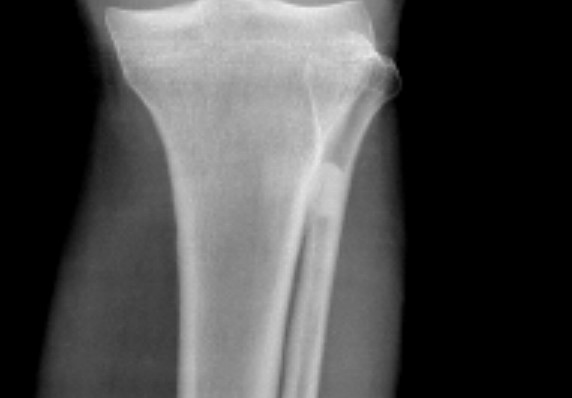

标题: X6255:男 40

外伤就诊

腓骨上段髓腔内高密度应是???

正位怎么看都有与胫骨重叠密度影,但侧位又那么干净利索,如果是外凸瘤的话,难道就垂直得这么好?

致密性骨瘤-------骨岛

支持 腓骨上段内生骨瘤。